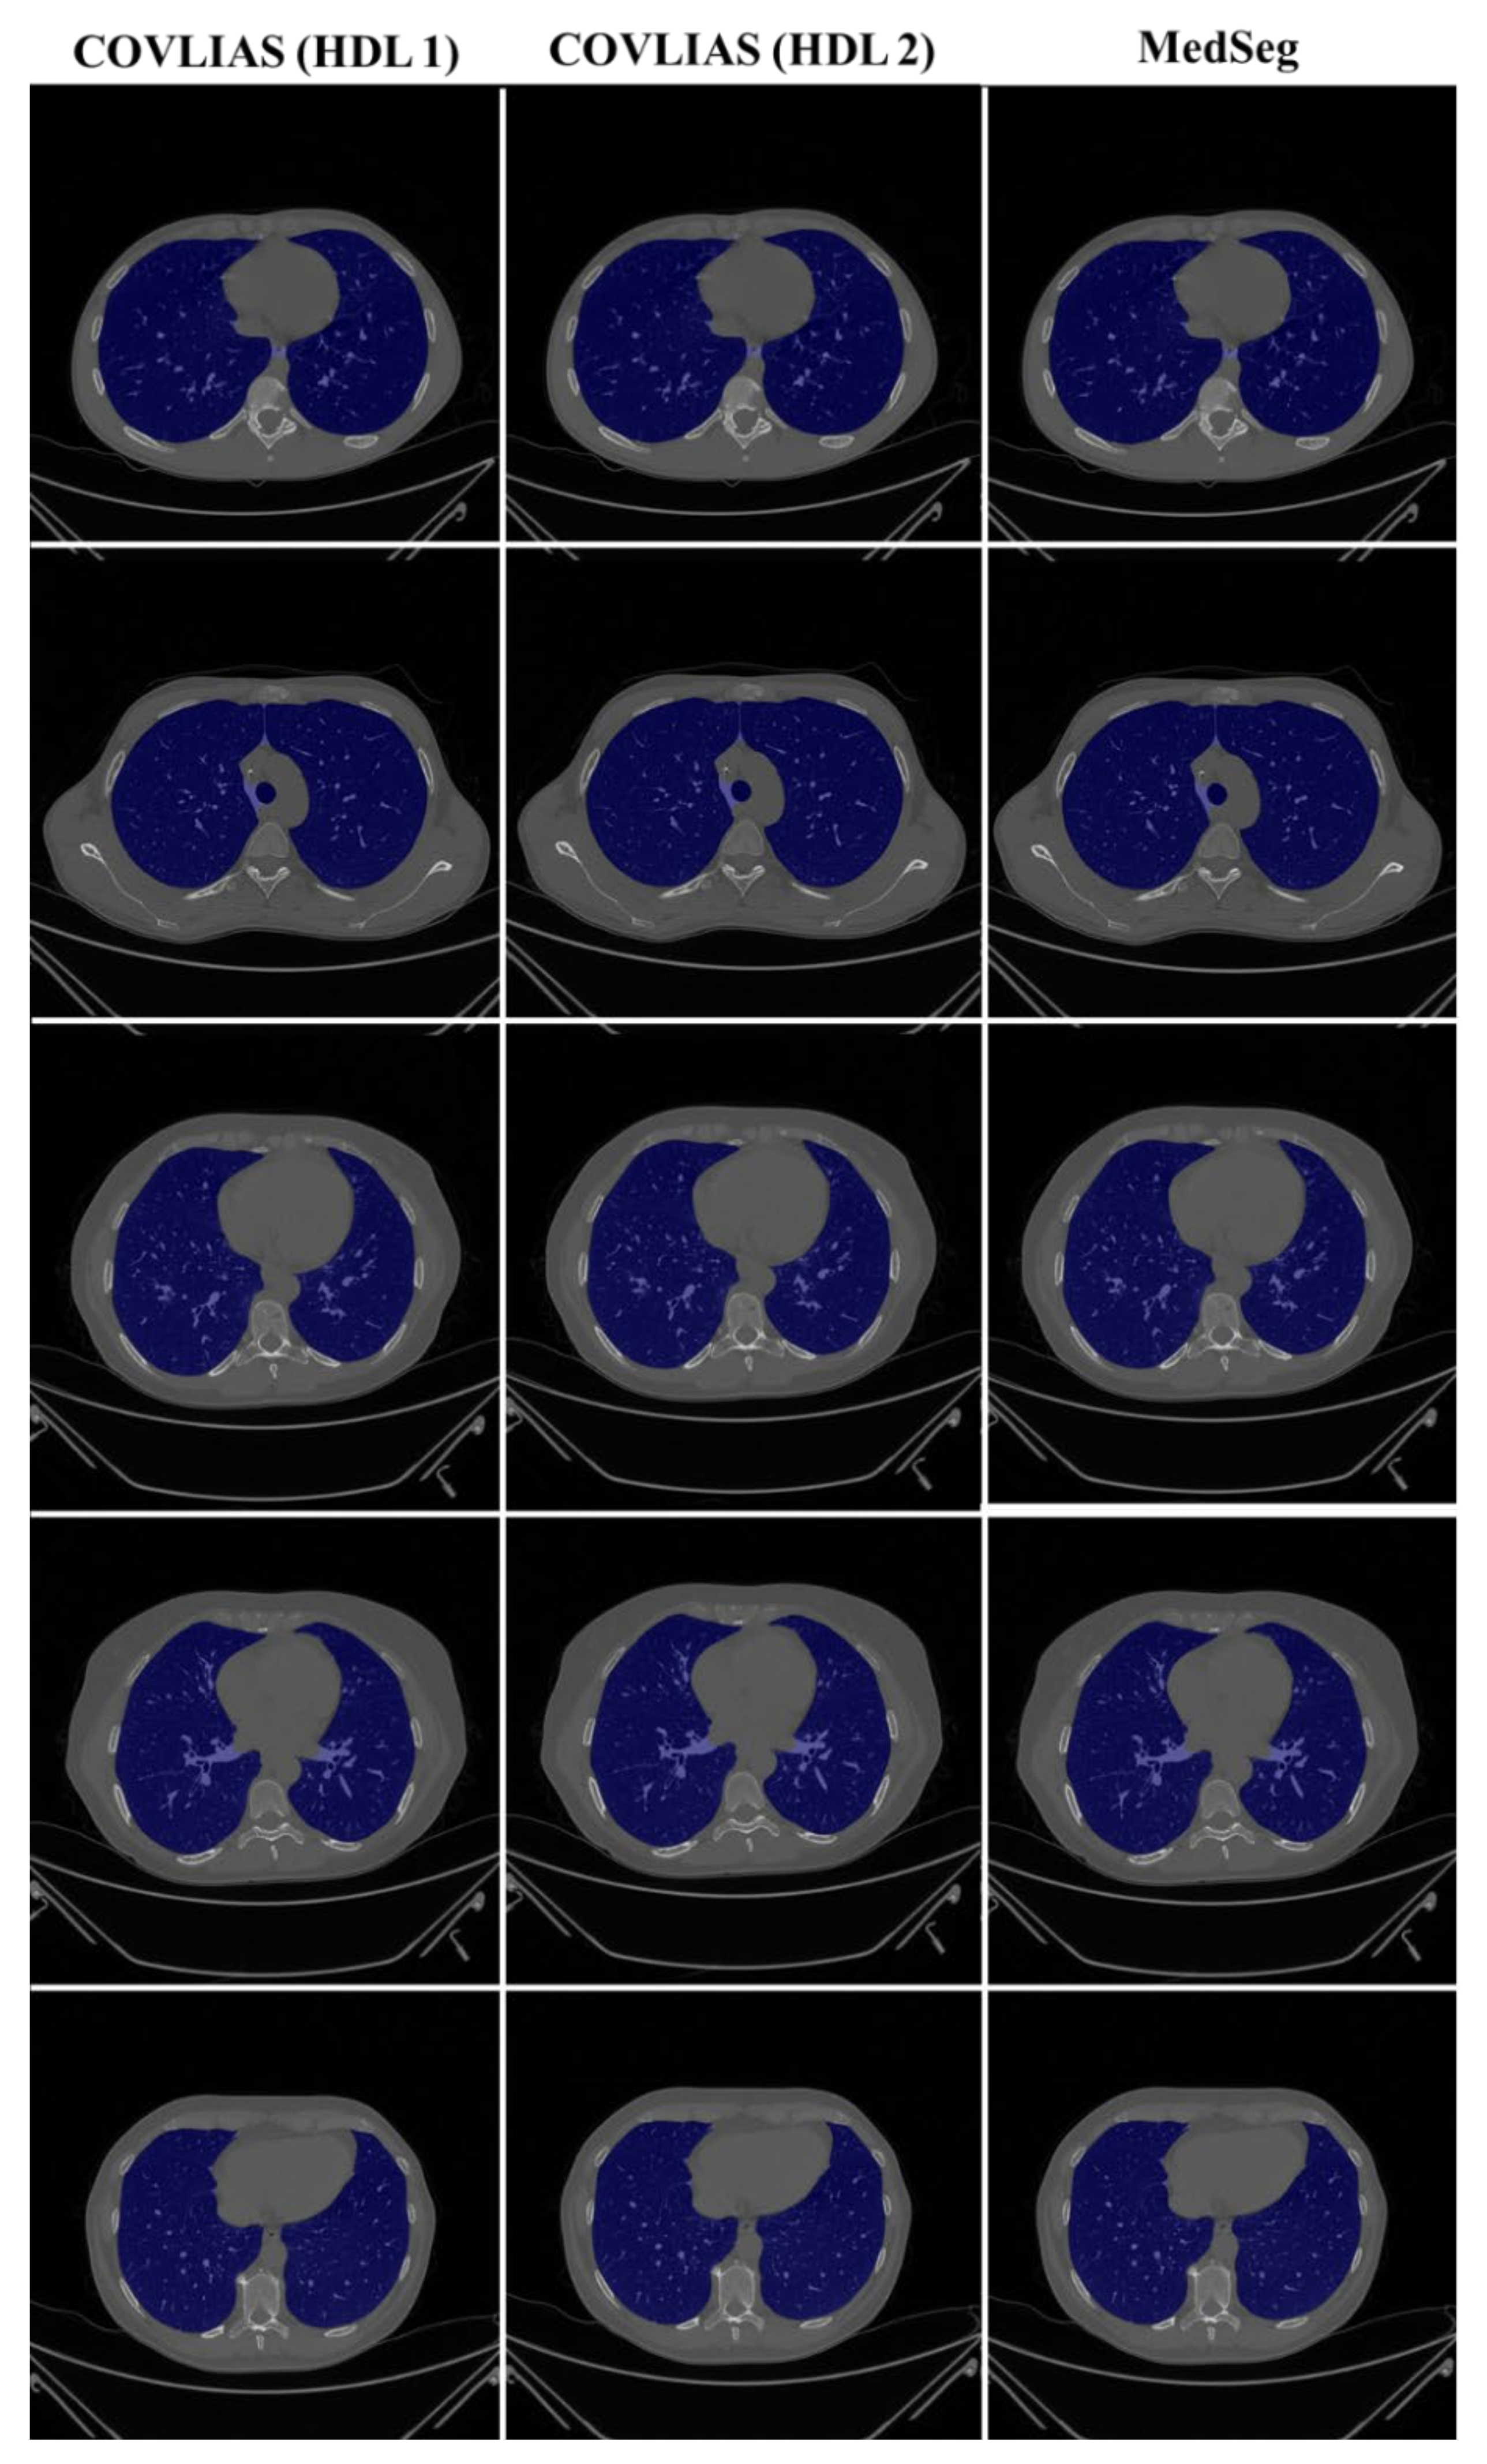

4.1. Performance: COVLIAS vs. MedSeg